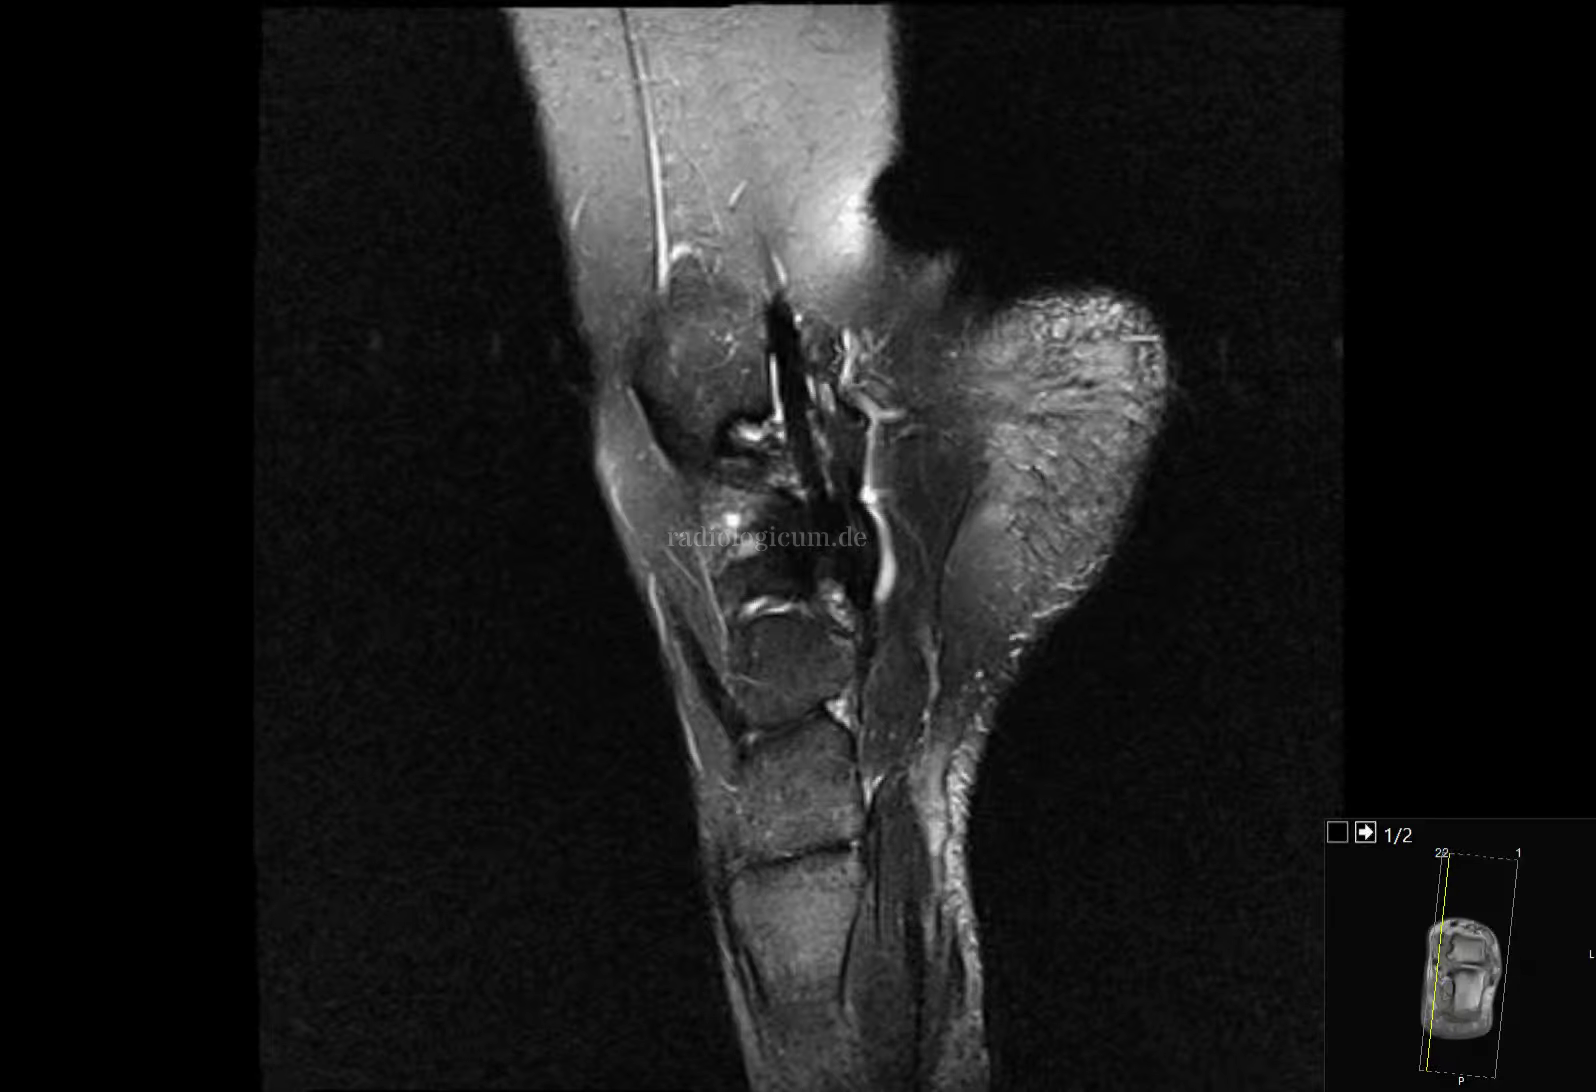

Os naviculare secundarium - Syndrom December 21, 2020Muskuloskelett apRtg sagPDfs traPDspair Headings Dieser Fall wurde noch nicht annotiert.